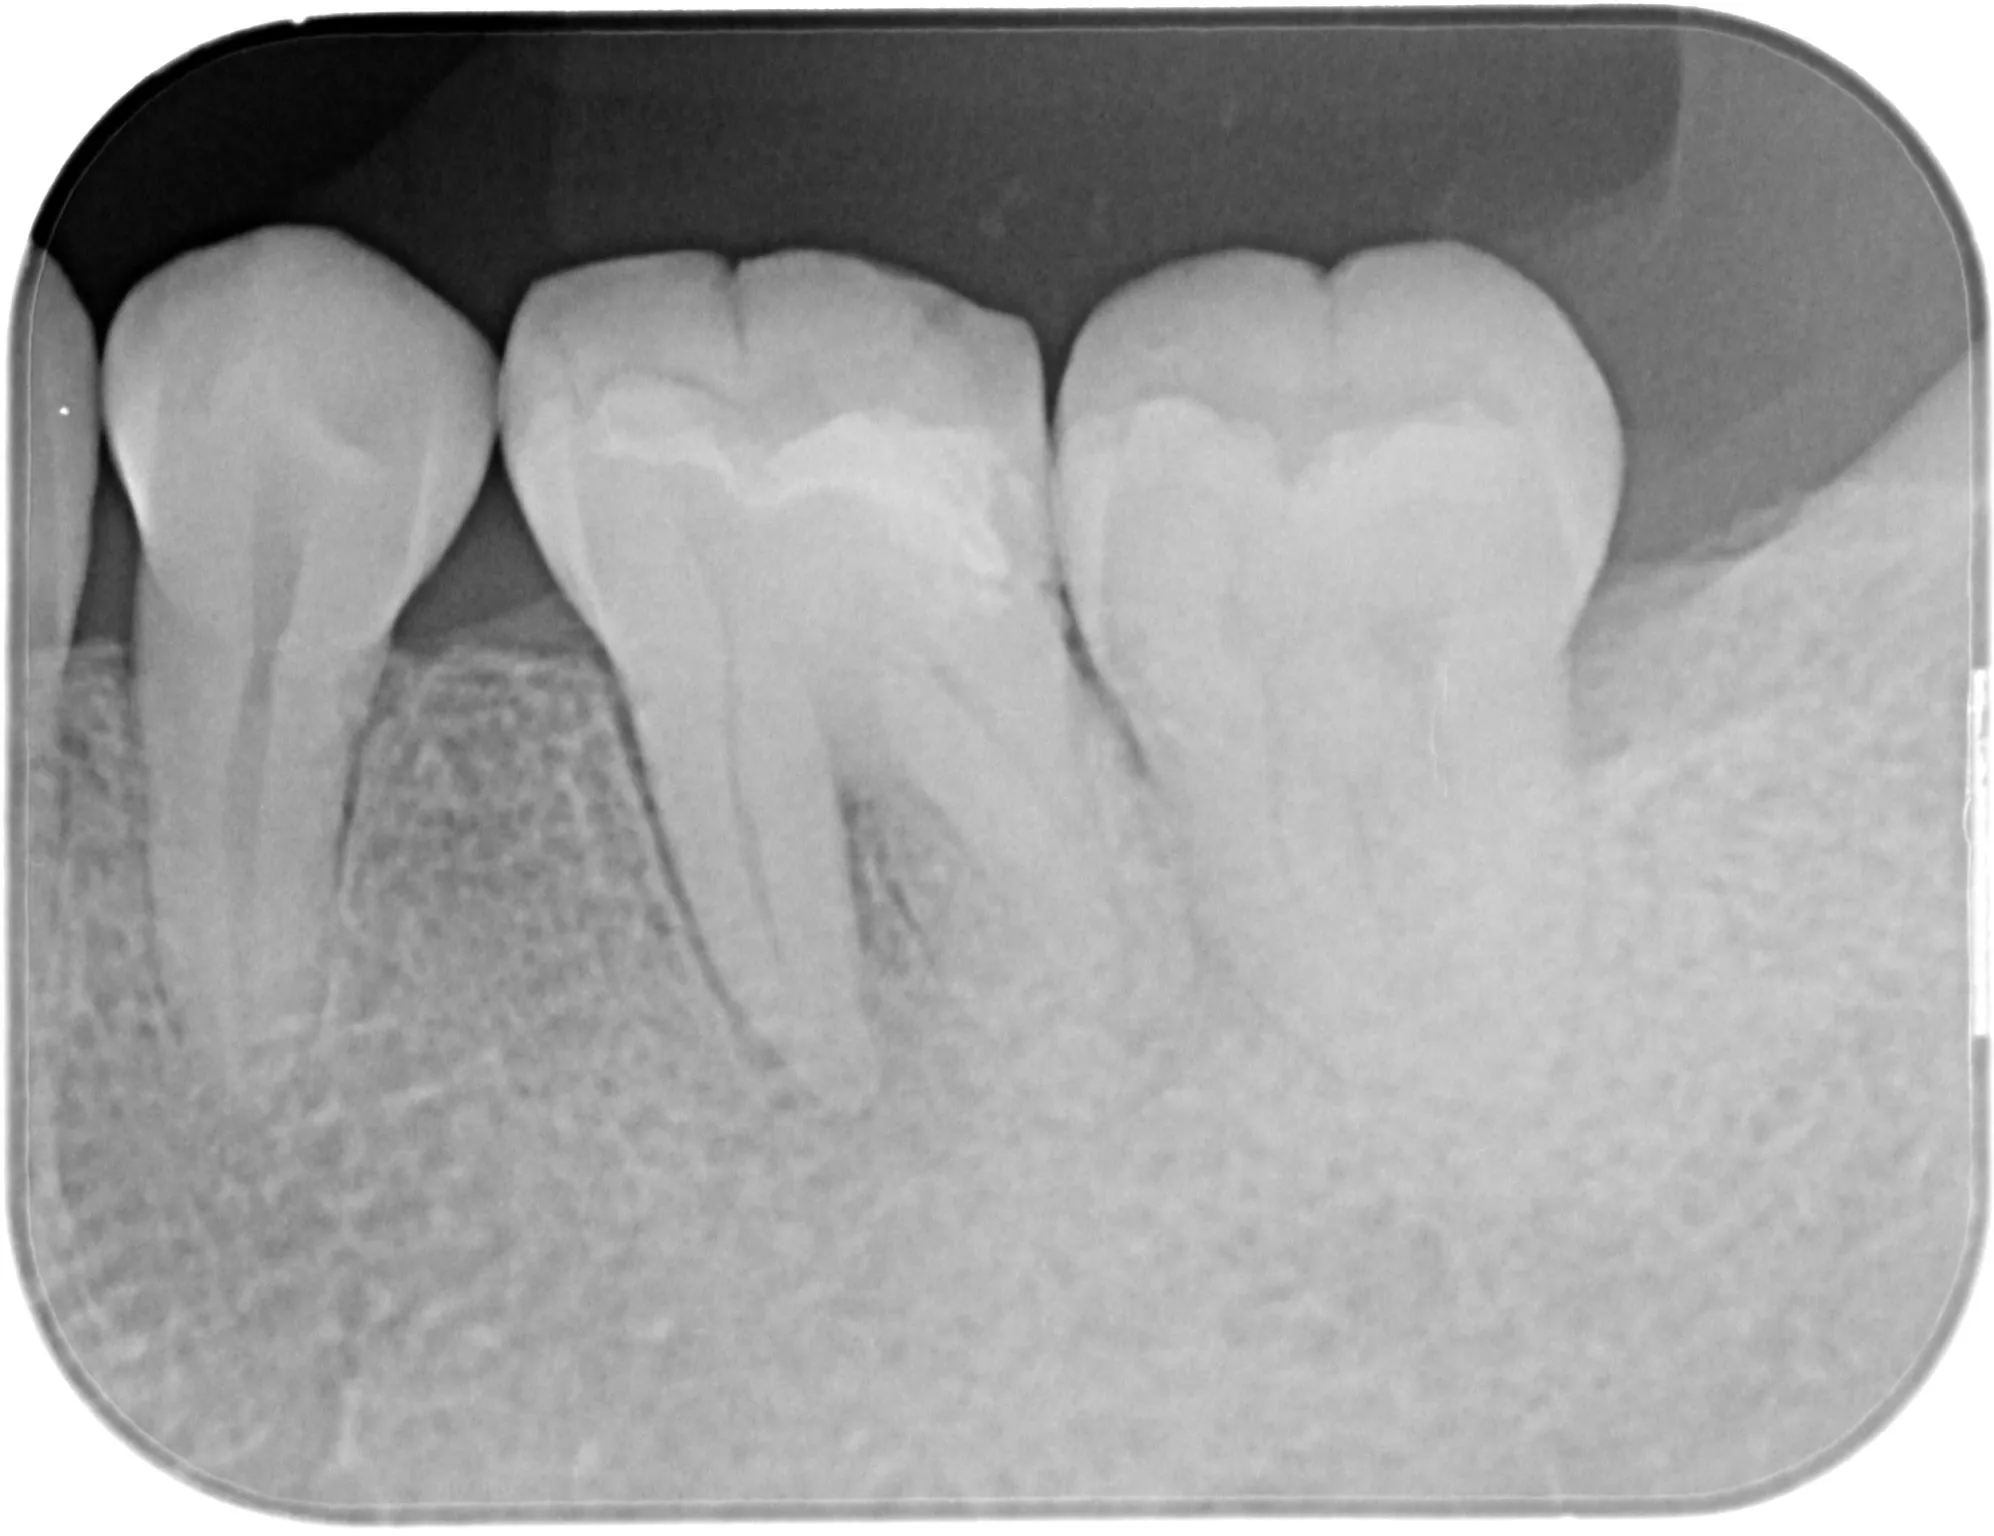

治療前